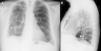

En esta revisión narrativa se describen las principales etiologías, características clínicas y tratamiento de los derrames pleurales de naturaleza benigna que, característicamente, pueden persistir en el tiempo: quilotórax y derrames de colesterol, pulmón no expansible, derrame pleural reumatoide, empiema tuberculoso, derrame pleural asbestósico benigno y síndrome de las uñas amarillas.

In this narrative review we describe the main aetiologies, clinical characteristics and treatment for patients with benign pleural effusion that characteristically persists over time: chylothorax and cholesterol effusions, nonexpansible lung, rheumatoid pleural effusion, tuberculous empyema, benign asbestos pleural effusion and yellow nail syndrome.